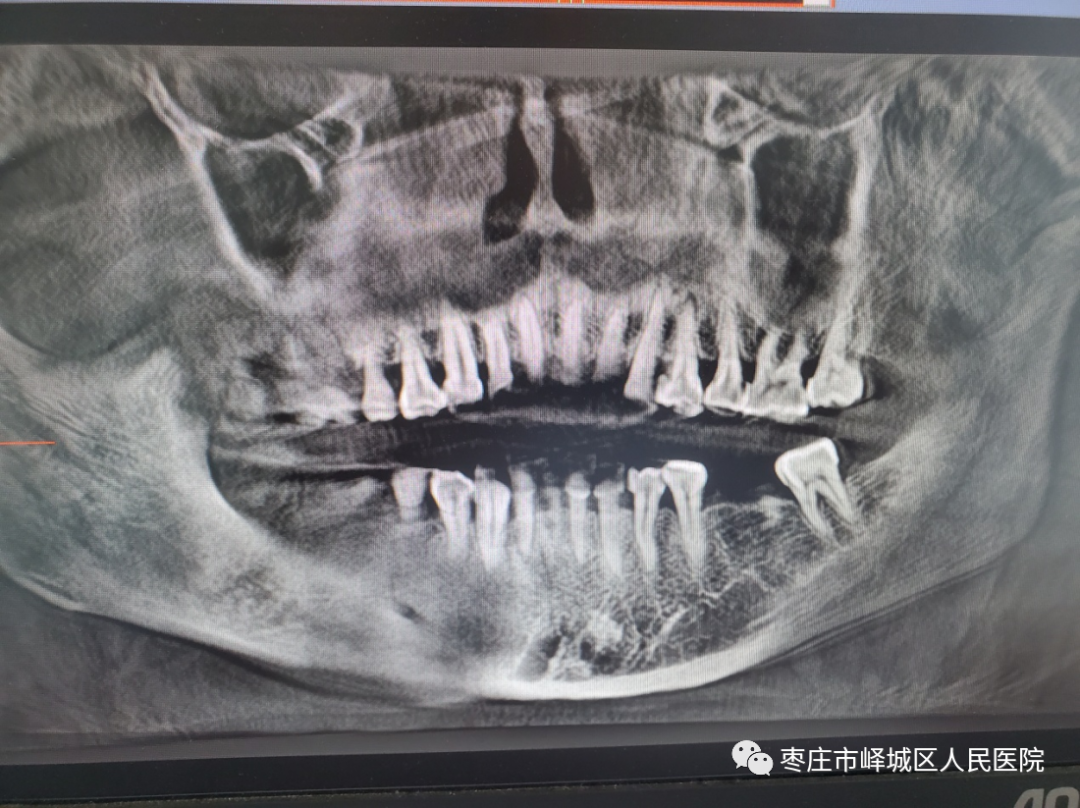

牙体牙髓

由于口腔牙齿的排列不在一个平面上,且具有一定的生理弧度,普通X线往往使图像相互重叠,CBCT的三维成像对牙体、牙周膜等微细结构显示更加清晰。可以帮助医生了解断根,评估牙根内吸收情况及根管钙化等,能用于根管治疗前寻找根管,术后评估根管充填情况等。